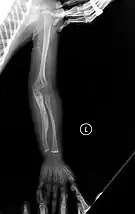

Diagnosis is typically based on medical imaging, including plain X-rays, and symptoms. In severe OI, signs on medical imaging include abnormalities in all extremities and in the spine.[97] As X-rays are often insensitive to the comparatively smaller bone density loss associated with type I OI, DEXA scans may be needed.[5]: 1514

An OI diagnosis can be confirmed through DNA or collagen protein analysis, but in many cases, the occurrence of bone fractures with little trauma and the presence of other clinical features such as blue sclerae are sufficient for a diagnosis. A skin biopsy can be performed to determine the structure and quantity of type I collagen. While DNA testing can confirm the diagnosis, it cannot absolutely exclude it because not all mutations causing OI are yet known and/or tested for.[83]: 491–492 OI type II is often diagnosed by ultrasound during pregnancy, where already multiple fractures and other characteristic features may be visible. Relative to control, OI cortical bone shows increased porosity, canal diameter, and connectivity in micro-computed tomography.[98] OI can also be detected before birth by using an in vitro genetic testing technique such as amniocentresis.[99]